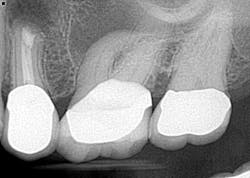

Case report A healthy 61-year-old female presents with a chief complaint of pain and discomfort in the upper left quadrant. A radiograph revealed a large radiolucency at the apex of tooth No. 12. An irregular root apex was also noted. Clinically No. 12 was sensitive to percussion and palpation in the buccal vestibular area. There was no response to cold. Diagnosis was necrotic tooth No. 12 with associated periapical abscess. RCT was recommended and the patient was referred to a specialist for completion. RCT was completed — no complications were noted and the prognosis was given as good. (Figs. 1 and 2) The patient was placed on recall by the endodontist for reevaluation of the lesion in 12 months.Fig 1. Fig. 2Eight months later, the patient presented back to the office stating that she felt pressure again in the upper left area. A radiograph of No. 12 showed an increased radiolucency around the apex of tooth No. 12. Furthermore, there was a draining fistula in the buccal vestibule. Diagnosis was persistent infection/disease, likely due to the initial presentation and presence of the cyst. (Fig. 3)

Fig. 3The patient did not want to lose her tooth and was referred back to the specialist for an evaluation and consideration of options. It was discussed and recommended that the patient have root end resection with a root end filling (apicoectomy). She agreed, and the treatment was completed. There was suspicion as to the nature of the pathology of the cyst-like lesion, so it was sent out for biopsy. Diagnosis was chronic, localized osteitis and actinomyces colony. Conclusively, the source of the infection was eradicated but the presence of the actinomyces microorganism was enough to sustain a chronic infection post-initial RCT. (Fig. 4)

Fig. 4A two-month follow-up with the patient revealed a recovery of the area with loss of pressure and pain. A radiograph of the area showed initial stages of healing and bone recovery. She has been placed on a recall program for continuous assessment of the area. Prognosis is good. (Fig. 5)